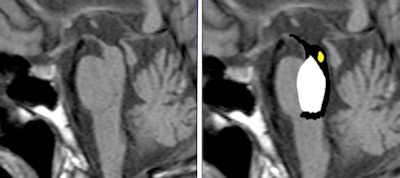

An example of these useful signs is the "penguin" seen in an MRI of the brain. More than amusing, the penguin is an interesting radiological sign seen in patients with progressive supranuclear palsy (PSP), noted Arora. It refers to atrophy of the midbrain tegmentum, with a relatively preserved pons on midsagittal T1-weighted images. The "penguin sign" can be helpful in distinguishing progressive supranuclear palsy from multisystem atrophy and Parkinson's disease.